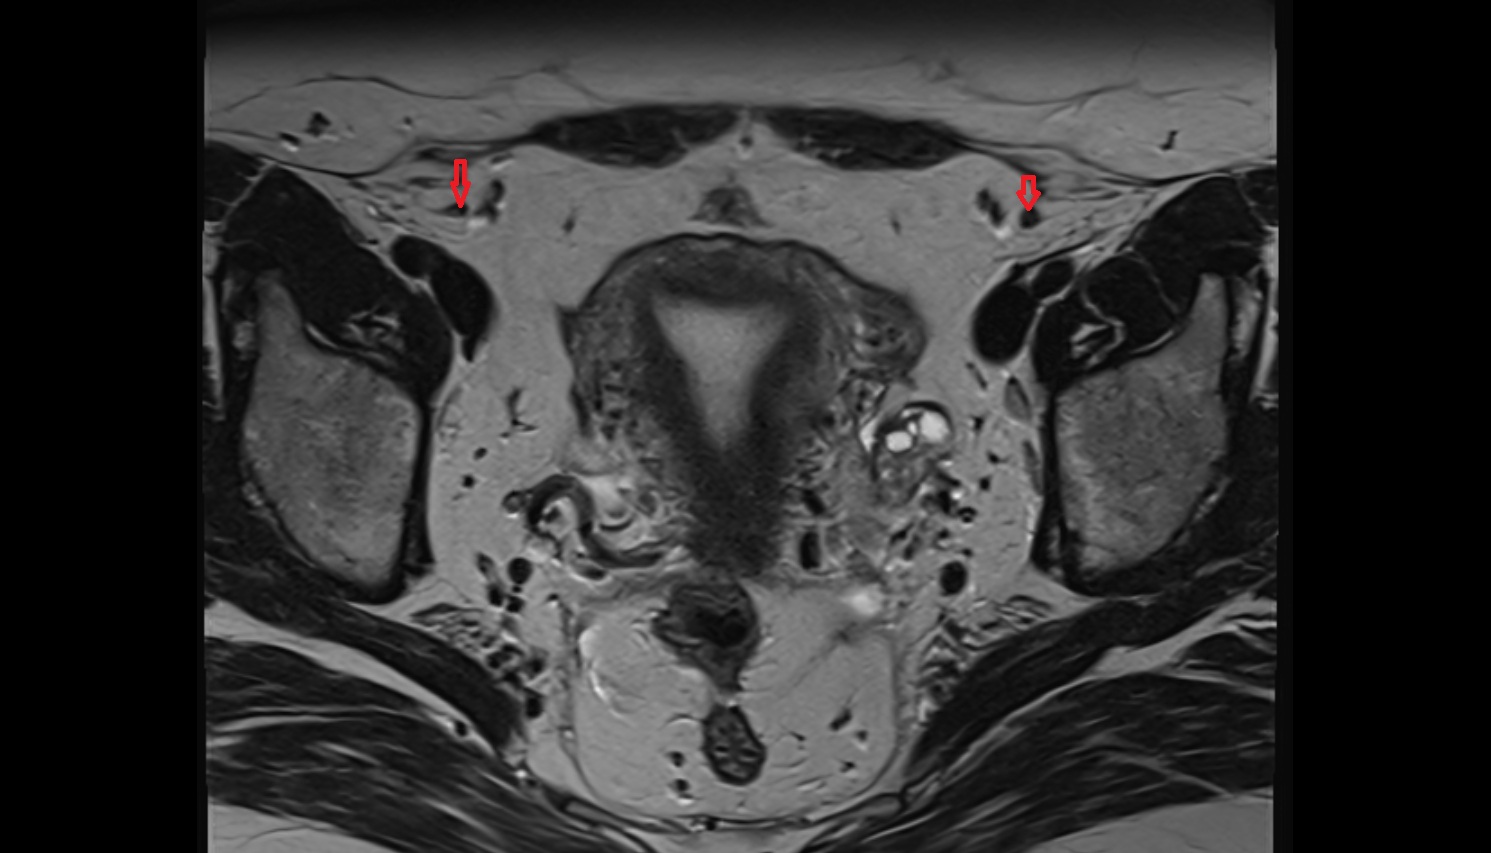

- Intermediate lacunar external iliac lymph nodes

- External iliac lymph nodes

- Obturator lymph nodes